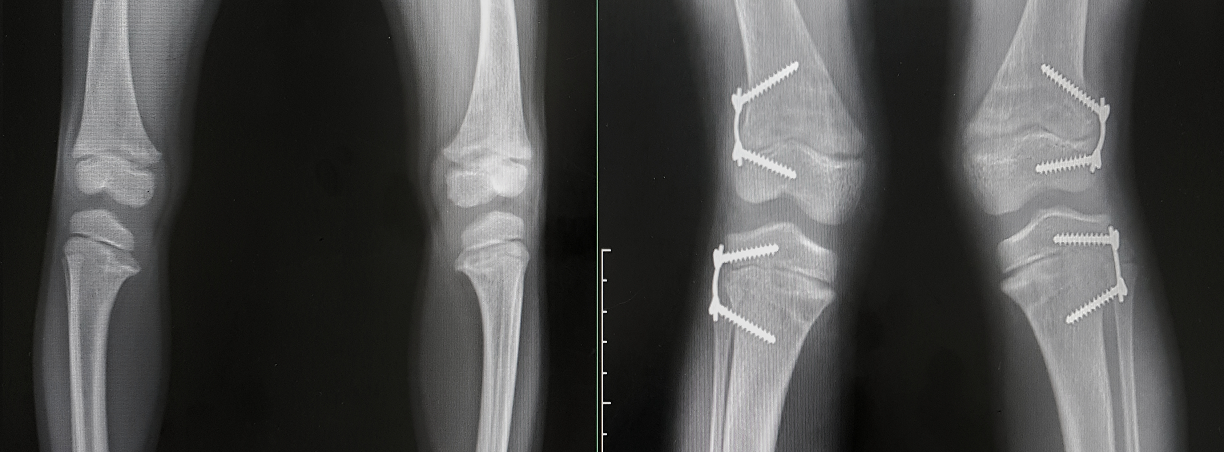

A seconda della severità di varismo e valgismo, le strategie terapeutiche possono essere diverse, fino ad arrivare all’operazione chirurgica. Solitamente si tende ad adottare delle strategie conservative, per ricorrere alla chirurgia solo nei casi più gravi.